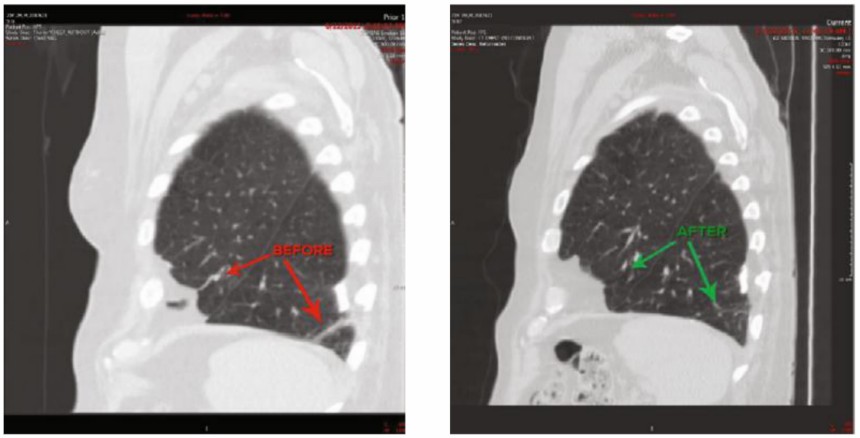

Placental mesenchymal stem cell exosome-derived multiple allogeneic protein paracrine signaling (P-MSC-Exo-MAPPS) by reducing inflammatory cytokines (TNF-α, IL-1β, IL-12, and IFN-γ), and increasing IL-10 and IFN-γ Regulatory T cells (Tregs) reduce COPD-related lung inflammation. Furthermore, P-MSC-Exo-MAPPS treatment significantly improved the lung condition of 30 COPD patients, and none of them experienced any adverse effects.

Changes in COPD patients receiving exosome therapy. (Harrell, et al., 2020)Fig.3 Representative computed tomography images before and after 1 month of P-MSC-Exo-MAPPS treatment of COPD patients.3,4